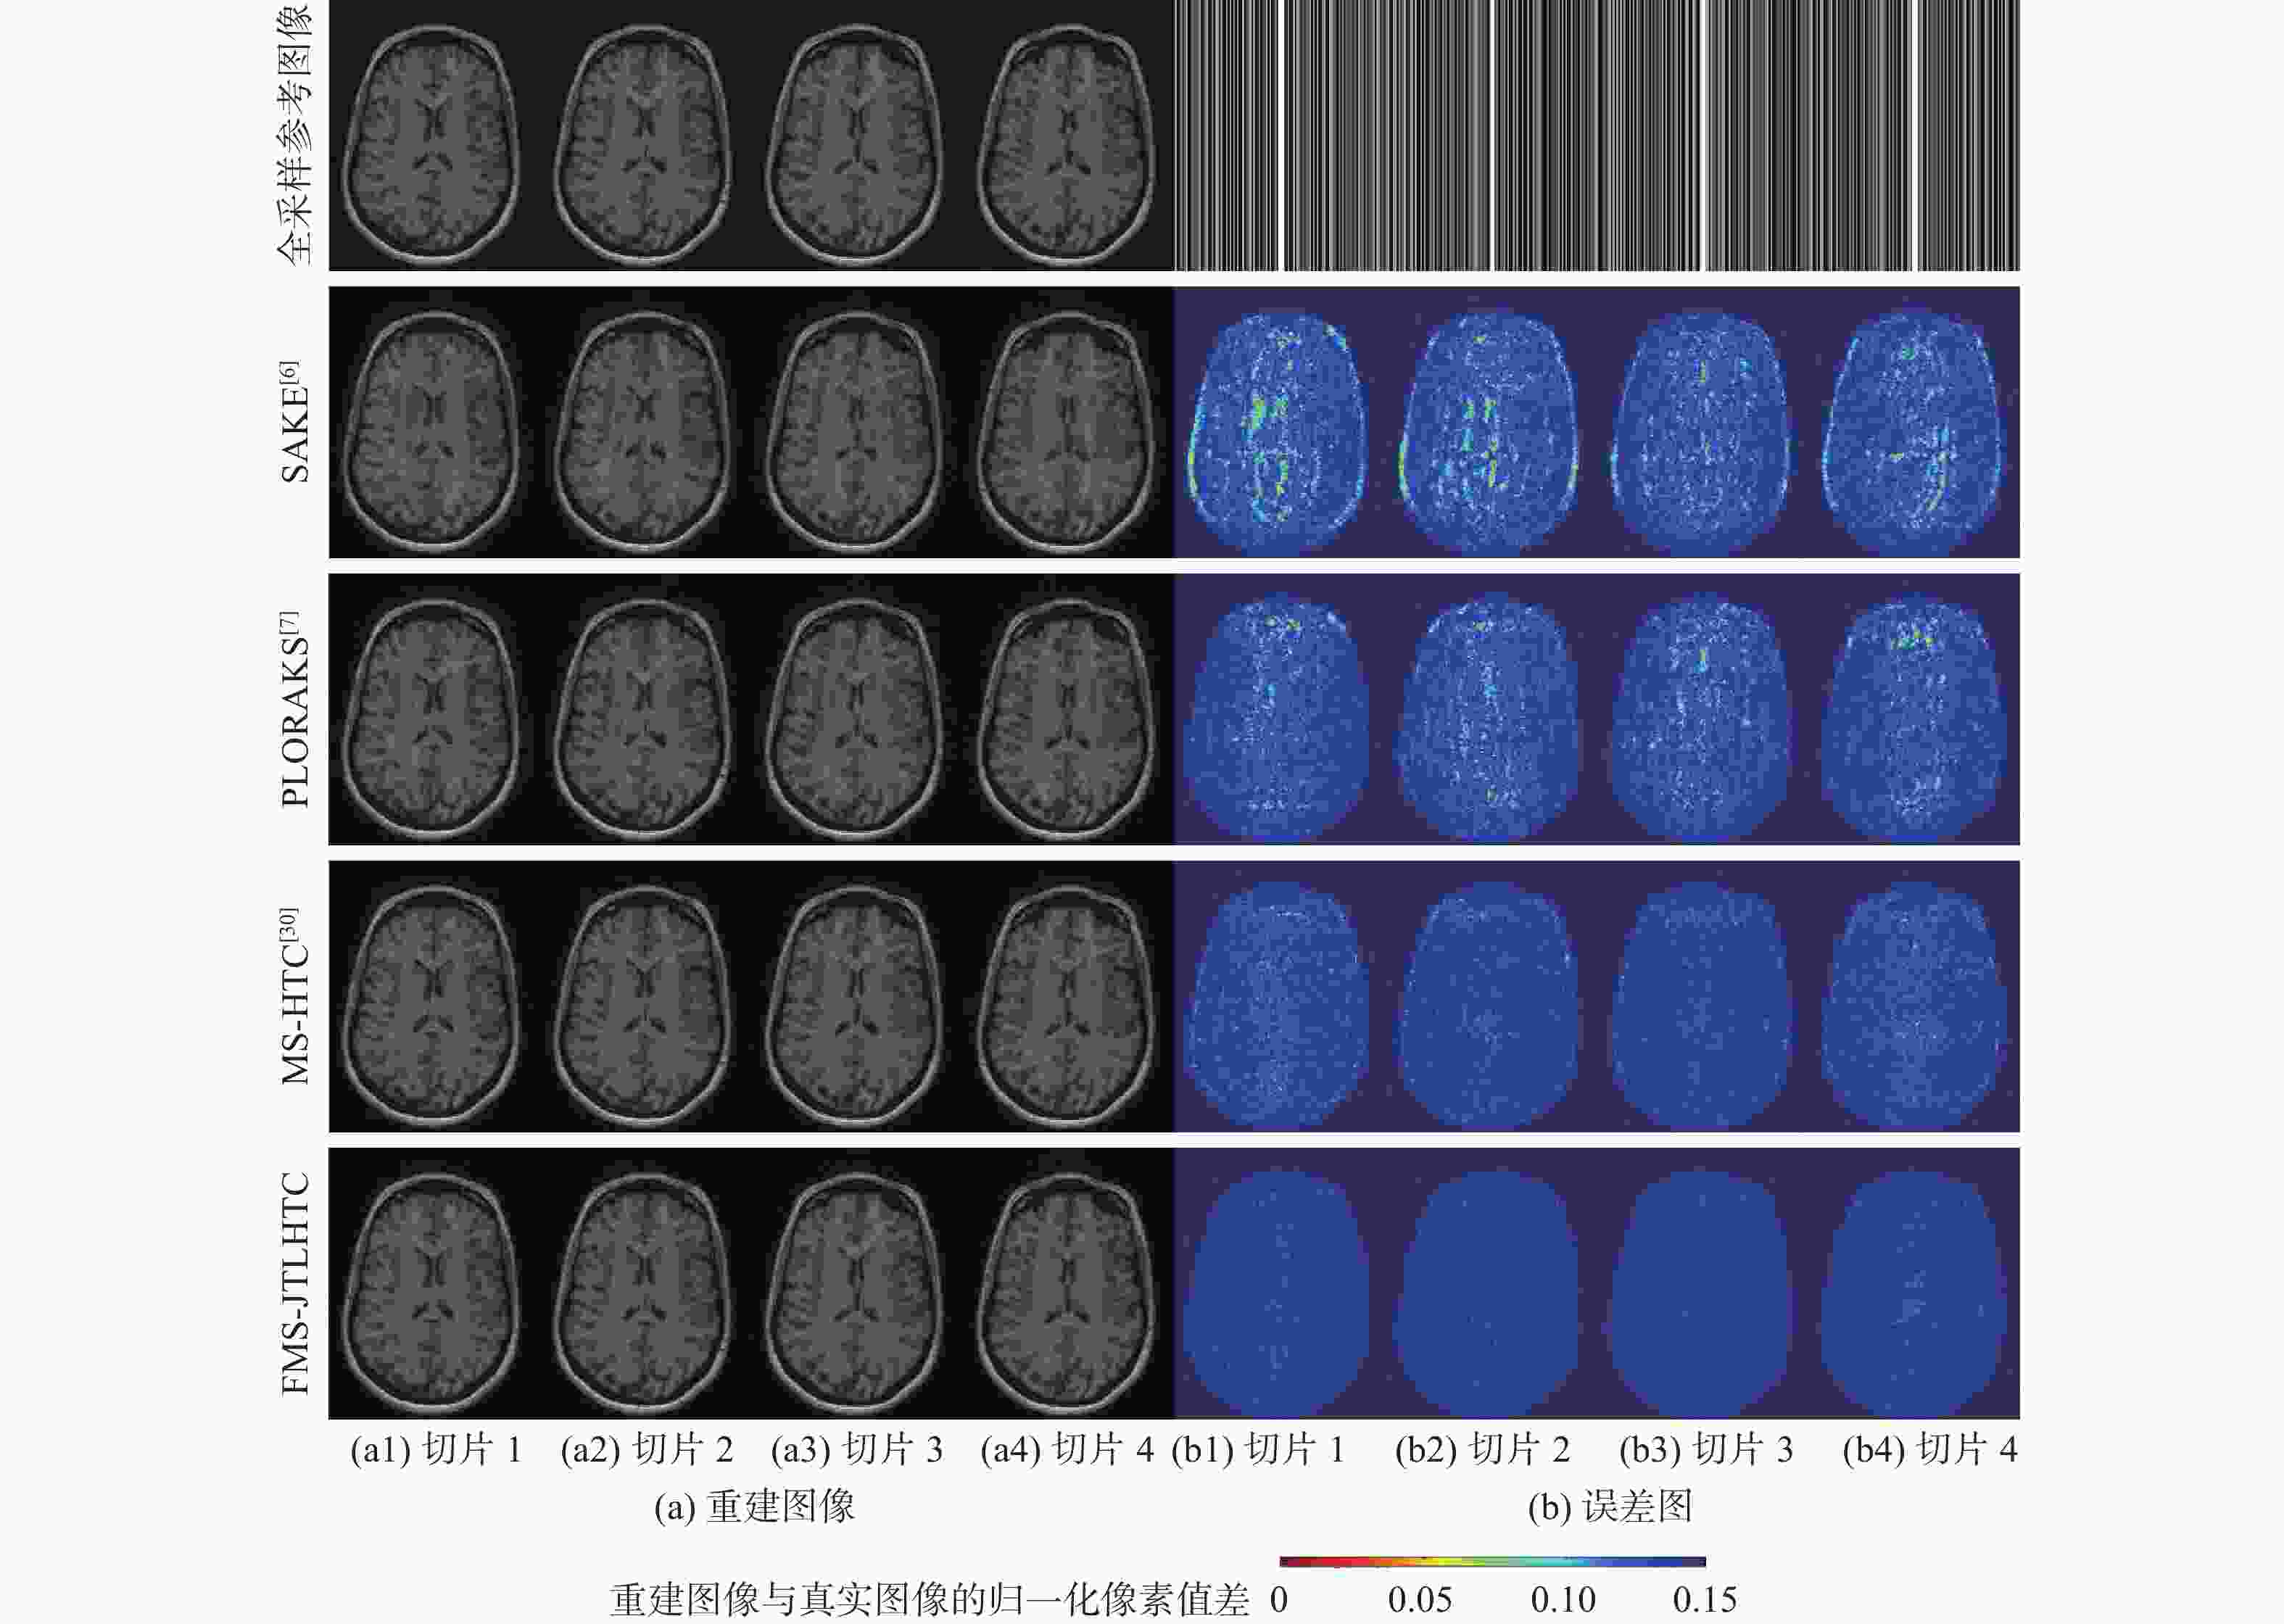

二维(2D)多切片磁共振数据在相邻切片之间具有高度的相关性,通过利用切片间的冗余性能够重建出更高质量的切片图像,但由于硬件条件的限制,2D多切片磁共振成像(MRI)需要耗费大量时间。为提高2D多切片磁共振图像的重建质量和重建速度,将联合稀疏变换学习正则项引入到多切片Hankel张量完成(MS-HTC)模型中,提出一种快速2D多切片磁共振成像重建(FMS-JTLHTC)算法。该算法使用交替方向乘子法对目标问题进行求解;引入快速迭代收缩阈值法加快收敛,并使用图形处理器对算法进行加速。使用4组脑部数据集在2种不同采样模式下进行实验,结果表明:FMS-JTLHTC算法的峰值信噪比(PSNR)相较于同时自动校准和K空间估计(SAKE)算法、并行成像数据的局部K空间领域的低秩建模(PLORAKS)算法和MS-HTC算法分别平均提高了4.04 dB、3.67 dB和2.07 dB,而且重建速度相比MS-HTC算法提高了14倍。

Abstract:Due to the significant correlation between neighboring slices in two-dimensional (2D) multi-slice magnetic resonance data, higher quality slice pictures can be reconstructed by taking use of the redundancy between slices. However, 2D multi-slice magnetic resonance imaging requires an amount of time. To improve the reconstruction quality and speed of 2D multi-slice (MRI) images, proposes a fast 2D multi-slice MRI reconstruction (FMS-JTLHTC) algorithm, which introduces the joint transform learning regular term into the multi-slice hankel tensor completion (MS-HTC) model. Prior to introducing the fast iterative shrinkage-thresholding procedure to accelerate convergence and utilize the graphics processing unit to speed up the procedure, the alternating direction method of multipliers is used to solve the objective issue. Experiments using four brain datasets in two different sampling modes show that the peak signal-to-noise ratio (PSNR) of the FMS-JTLHTC algorithm is improved by an average of 4.04 dB, 3.67 dB, and 2.07 dB compared to the simultaneous atuo-calibrating and K-space estimation (SAKE), low-rank modeling of local K-space neighborhoods with parallel imaging data (PLORAKS) and MS-HTC algorithms, respectively, the reconstruction speed is improved by a factor of 14 compared to the MS-HTC algorithm.